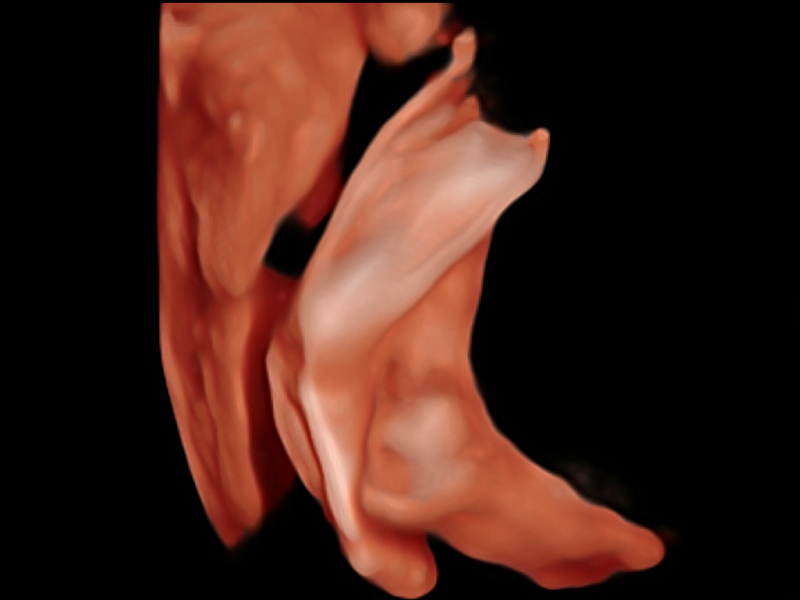

• 产科扫查助手S-Fetus

S-Fetus基于大数据深度学习算法,能够帮助您在产前筛查过程中智能识别胎儿标准切面、自动测量并录入报告。一个按键,即可智能、精准、高效地获取胎儿生理指标,极大简化您的产科检查操作。

• 产科自动测量Auto OB

可快速对产科扫查切面完成胎儿生理学参数的自动测量,减少操作者按键次数,大幅提升检查效率。